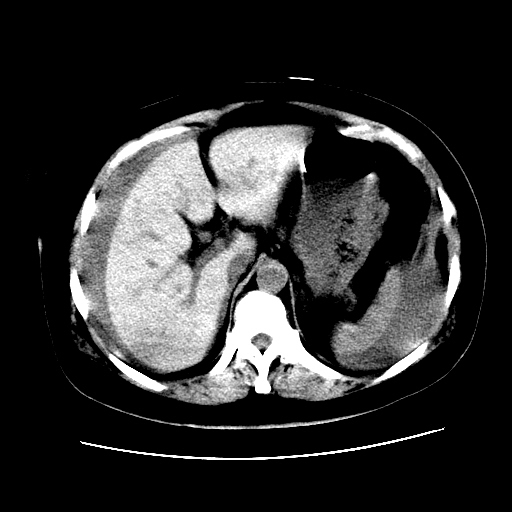

f,45y.怀孕4月晕倒,b超提示死胎,有手术结果,请展开讨论后明天告诉。

膈下-肠间隙内见气体密度影,子宫轮廓显示不清,宫腔-腹腔积液,首选考虑---子宫破裂出血。

1)宫腔妊娠。2)子宫破裂出血,腹腔及盆腔积血。

肝小可能是肝硬化,也可能是正常或畸形

腹腔积液,怎么来的可能是肝来的,也可能是别的来的

盆腔积液考虑破裂,至于说那裂了,那要不是宫外孕就是子宫破了要是宫外动就是宫外孕破裂出血

感谢同行们的高见。手术结果:子宫破裂出血。

我们的诊断是:腹、盆腔积液(考虑腹盆腔脏器破裂出血);宫腔妊娠。让人纳闷的是当时我们没有经验,现在回头看看分析:4月宫腔妊娠:1、洋膜囊不可能紧贴胎体这么小;2仔细看看子宫后壁肌层模糊不清;3腹、盆腔液体来源原因?4、45岁高龄妊娠有晕倒。由此可大胆诊断:宫腔妊娠子宫破裂出血。